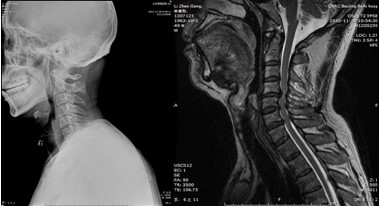

患者,男性,49岁,主因“行走不稳2个月伴右前臂麻木1个月”入院

2月前开始出现双下肢行走不稳,有踩棉花感,行走距离受限。1月前出现右侧前臂及手指麻木感。3周前诊断为“颈椎病”,保守治疗无改善,行走不稳症状加重

影像检查结果: